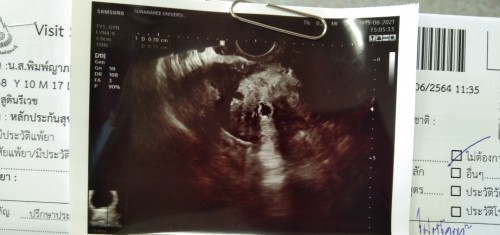

แบบนี้คืออะไรคะ ไม่รุ้เลยค่ะ หมอบอกอาจจะท้อง รอผลเลือดอยู่ค่ะ

น่าจะเป็นถุงการตั้งครรภ์นะค่ะแม่